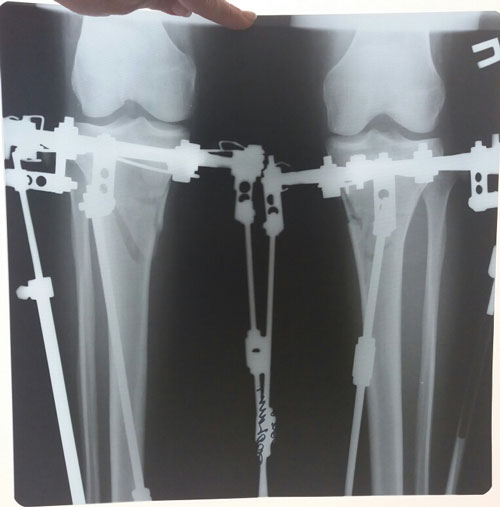

Исходник - 26 лет. Атырау

Дата операции - 16.06.2018г.

Дата снятия аппаратов 29.08.2018г.

Срок сращения 72 дня.